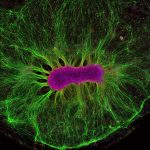

Brain-on- a-Chip

Neural stem cells have the ability to form all the different cell types found in the nervous system. Here, researchers are investigating how neural stem cells grow on a synthetic gel called PEG. After just two weeks, the stem cells (magenta) produced nerve fibers (green). These fibers grew away from the cell due to chemical gradients in the gel, teaching researchers about how their environment affects their structural organization. This work supports the Human-on- a-Chip project, which is addressing the inefficiency and cost of traditional drug testing. Researchers have devised ways of growing miniature organs on plastic chips, which they hope can be connected to represent the human body. This could be used to accurately predict the effectiveness and toxicity of drugs and vaccines and remove the need for animal testing in medical research. This image appears as a result of the partnership between Wellcome Images and the Koch Institute at MIT.

COLLIN EDINGTON AND IRIS LEE, © MASSACHUSETTS INSTITUTE OF TECHNOLOGY (MIT)